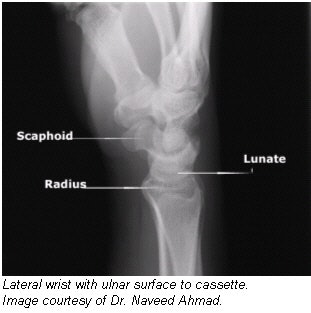

Positioning for lateral projection

- Seat the patient at the end of the radiographic table.

- Have the patient rest the arm and forearm on the table to ensure that the wrist is in a lateral position.

- Have the patient flex the elbow 90° to rotate the ulna to the lateral position.

- Center the cassette to the carpals, and adjust the forearm and hand so that the wrist is in a true-lateral position.

- CR: Perpendicular to the wrist joint.

Evaluation criteria

- Distal radius and ulna, carpals, and at least the midmetacarpal area should be visible.

- Long axis of the hand, wrist, and forearm should be aligned with long axis of IR.

- True-lateral position is evidenced by the following: Ulnar head should be superimposed over distal radius; proximal second through fifth metacarpals all should appear aligned and superimposed.

- Soft tissue and bony trabeculation should be visible.